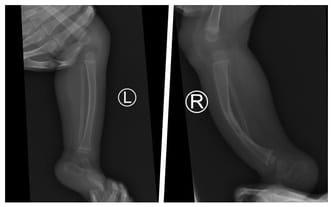

Wrodzony staw rzekomy goleni